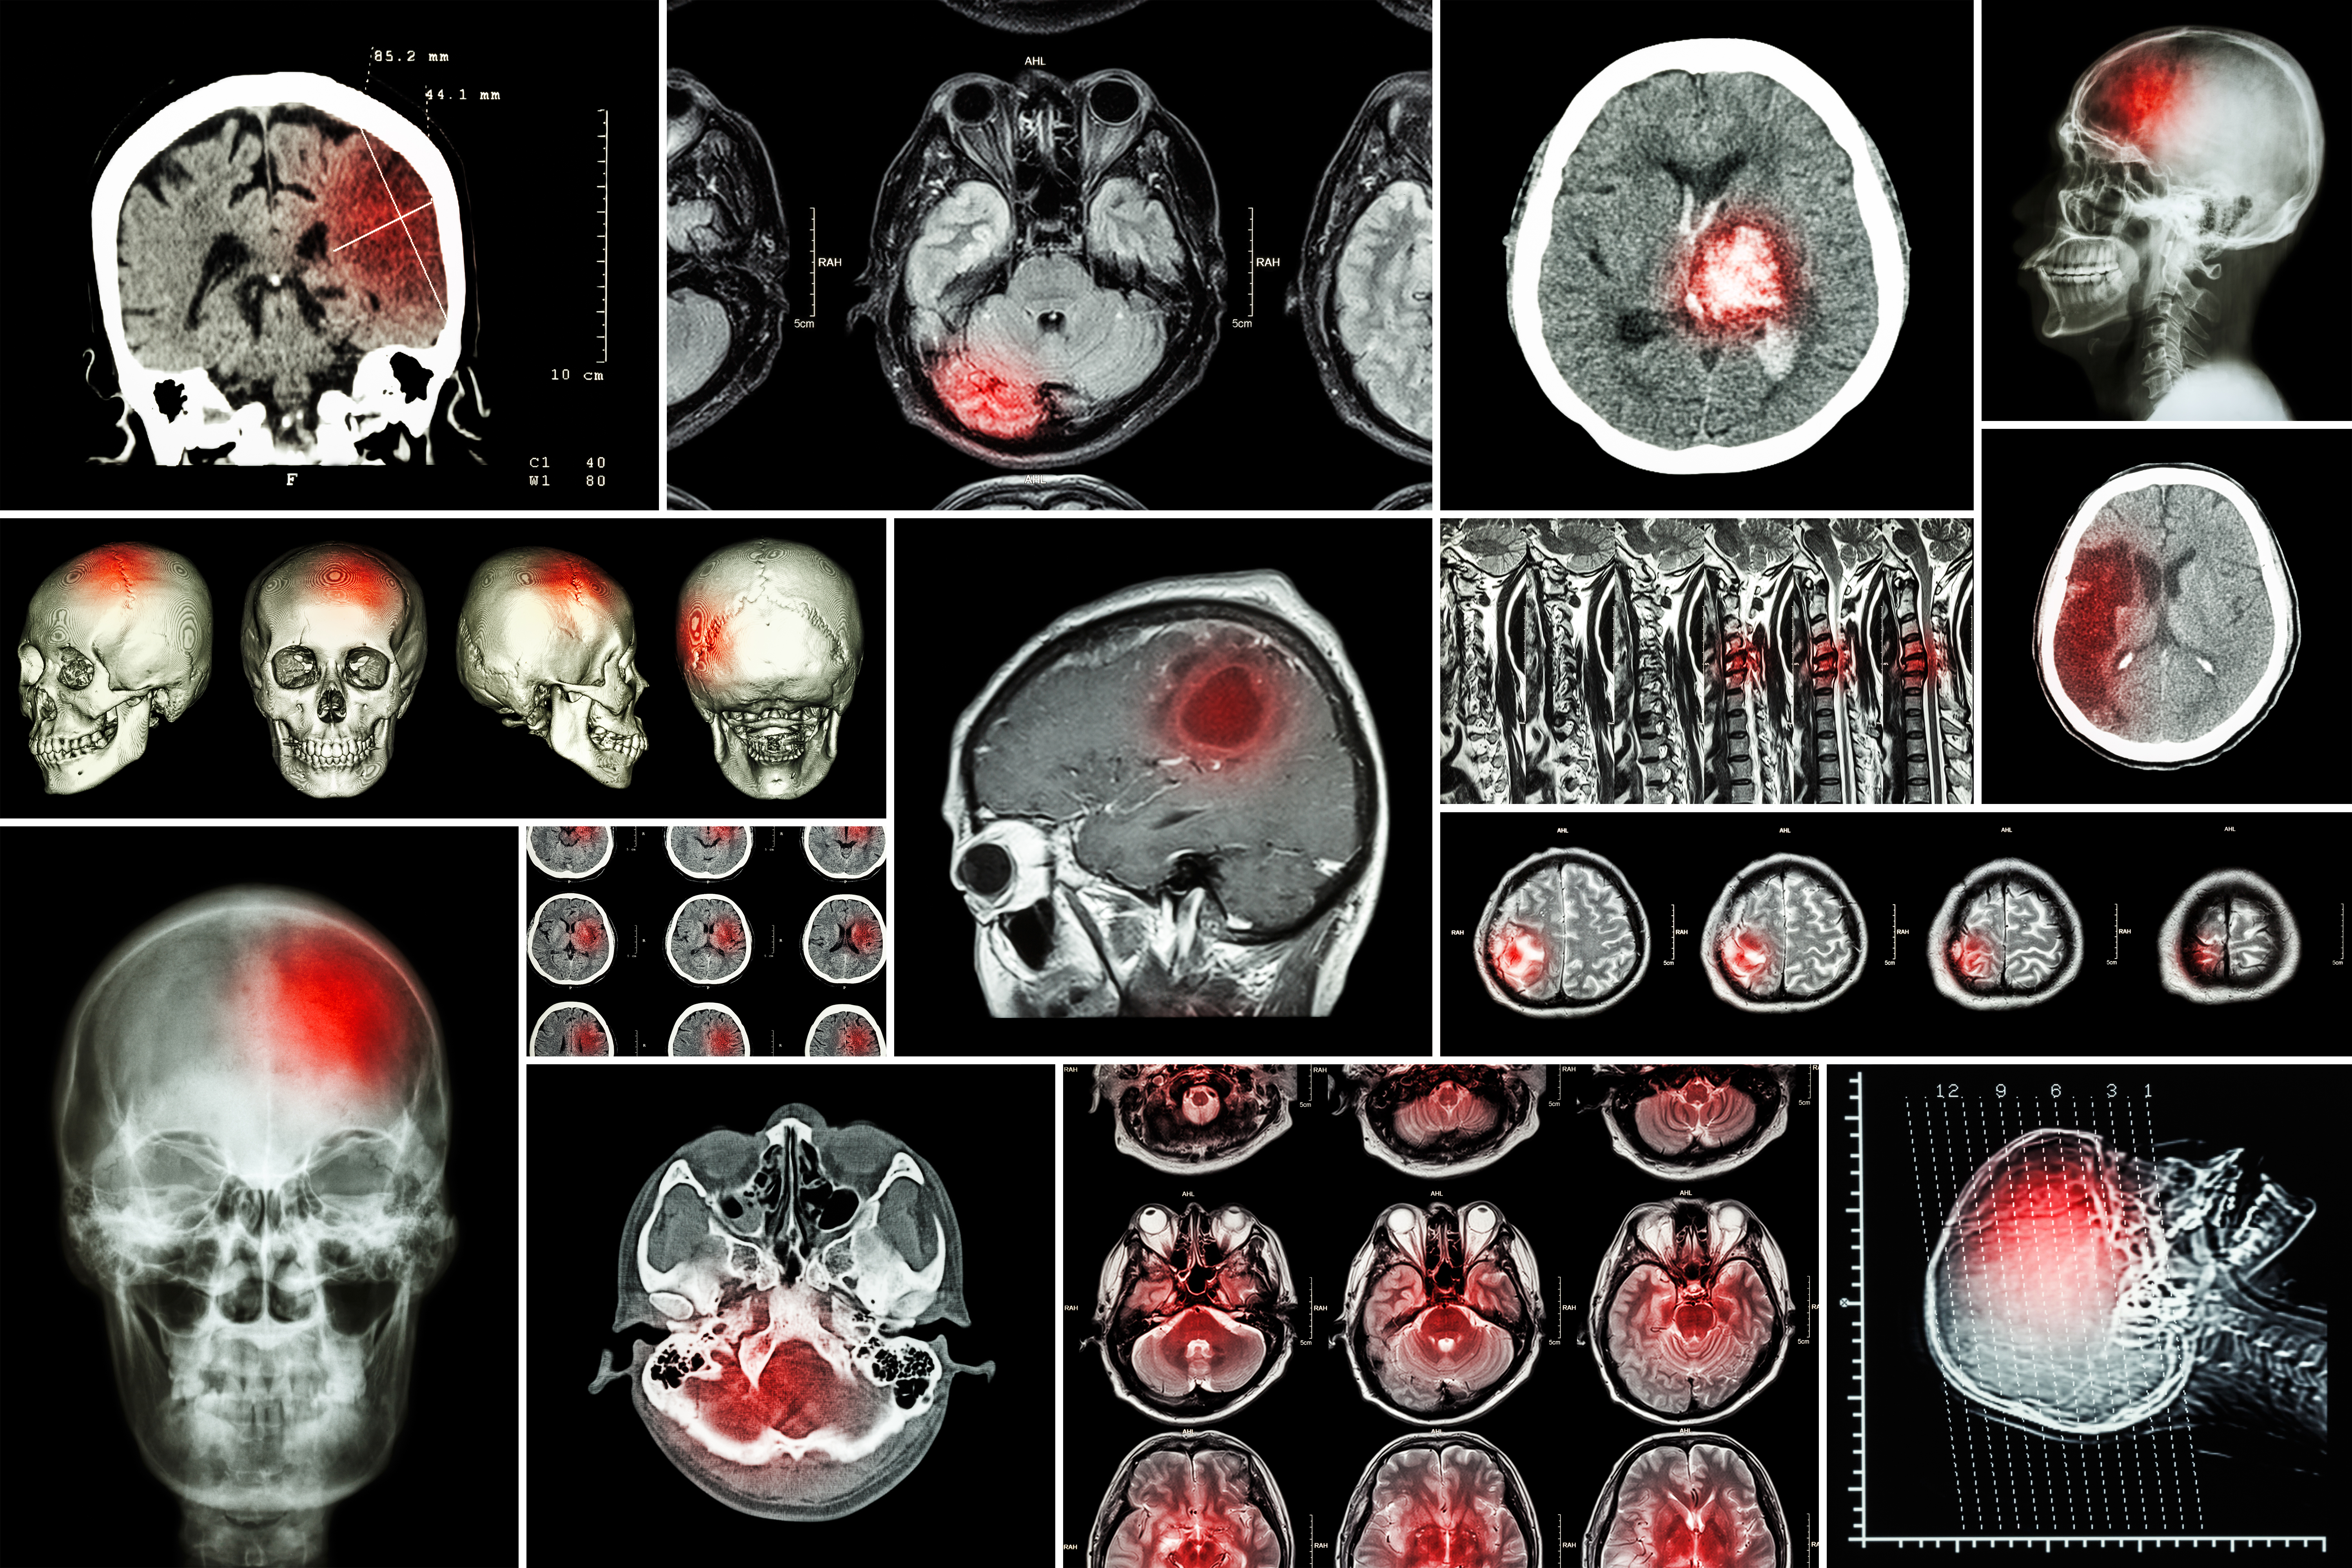

How a waste product of exercise protects neurons from trauma damage

Researchers led by EPFL have found how lactate, a waste product of glucose metabolism can protect neurons from damage following acute trauma such as stroke or spinal cord injury. Read more